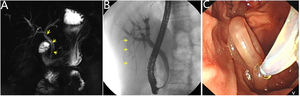

A 42-year-old female presented with a 3-day history of severe abdominal pain radiating to back, nausea and vomiting, without chills and fever. Physical examination revealed right epigastric tenderness without guarding. Laboratory test results showed total bilirubin and conjugated bilirubin level increased. Magnetic resonance cholangiopancreatography (MRCP) showed a hypo intense strip in the common and right intrahepatic bile ducts (Fig. 1A, yellow arrow). Endoscopic retrograde cholangiography (ERCP) found the ascaris had completely gone into right posterior intrahepatic bile duct (Fig. 1B, yellow arrow). We extracted the ascaris using a wire-guided basket without sphinterotomy (Fig. 1C, Video 1). The lady's pain was gone after the ascaris extraction and she was discharged two days later.

Video 1: ERCP revealed a long strip filling defect in the right posterior intrahepatic bile duct and the ascaris was extracted by a wire-guided basket without sphincterotomy.

A 42-year-old female presented with a 3-day history of severe abdominal pain. The bilirubin level increased slightly. MRCP showed a hypo intense strip in the common and right intrahepatic bile ducts. The ascaris was not visible at the duodenal papilla in duodenoscopy. After biliary intubation, cholangiography showed that no filling defect in the common bile duct. A filling defect was visible in right intrahepatic bile duct after injecting of contrast agent continuously. The guide wire was inserted into right bile duct. The basket failed to catch the filling defect. After injection of contrast agent again, a long strip filling defect appeared in the right posterior intrahepatic bile duct. The guide wire was inserted into the bile duct. The wire-guided basket was inserted into the posterior intrahepatic bile duct. The ascaris was caught and pulled out of the papilla successfully.